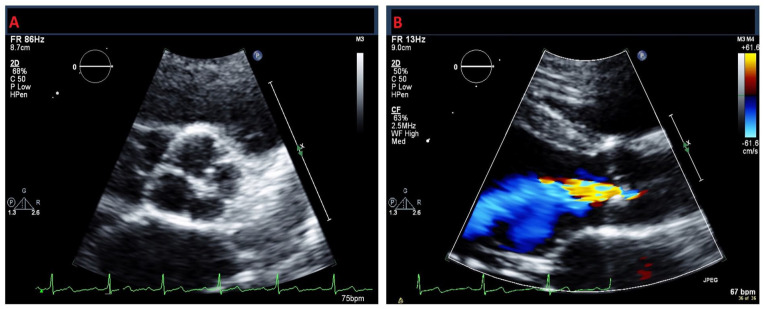

We describe a 30-year-old Caribbean-Black woman with a clinical presentation suggestive of a transient ischemic attack (TIA) with no conventional cerebrovascular risk factors, albeit with a newly diagnosed quadricuspid aortic valve (QAV) with moderate aortic regurgitation (AR). Although QAV is a recognized congenital cardiac defect, its association with TIA remains elusive. This case highlights the importance of considering potential atypical etiologies, such as QAV, in the evaluation and management of young patients presenting with cerebrovascular events.

Abstract Image